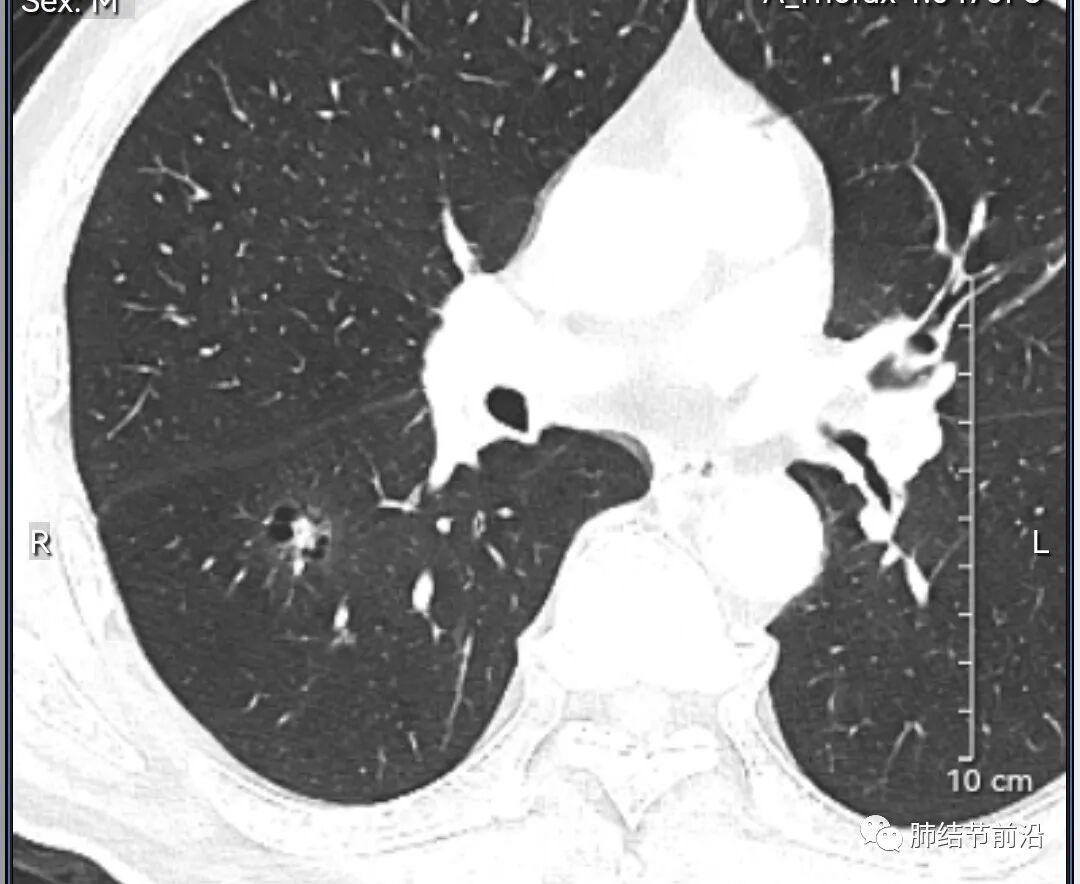

男性,67岁,重度吸烟史。CT发现右下肺囊腔。来看一下这个CT的特点:

该囊腔形态非常有特点,和常见的圆形肺大泡有很大的区别。

1.囊腔中央实性成分,周围有磨玻璃影。

2.囊腔中央有血管。

3.囊腔外周有分叶形态。

4.囊腔有胸膜牵拉。

出现这几种形态,CT可以确认恶性的腺癌。这个囊腔形成的机制,为肿瘤实性成分堵塞细支气管形成活瓣,肺泡内压力增高破裂行成,因此肺内血管成分保留。由于肺泡压力增高,而呈分叶状。另外,也有肿瘤的胸膜牵拉这一特点。

囊腔周围磨玻璃+囊腔中央血管为特征性表现。如果持续存在,几乎可以100%确认为早期肺腺癌。